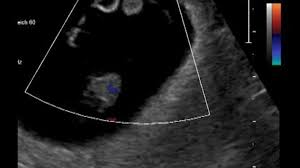

Abbildungen Und Graphiken Tipps Und Tricks Im Gyn Ultraschall Der Dottersack In Der Fruhschwangerschaft

Aber das sieht sehr nach dem berühmten Dottersack aus. Ähnliche Fragen zum Thema Schwangerschaft und Geburt. Ultraschall-Video der Woche Du bist schon ganz neugierig auf das erste Ultraschall-Video deines Babys.